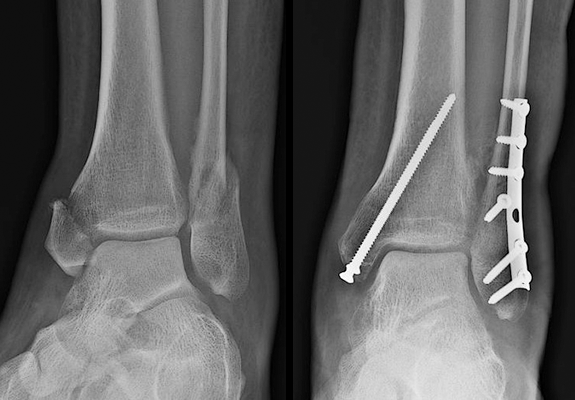

三、踝关节融合术

踝关节融合术于1879年被提出,多数学者迄今为止仍认为其是减轻患者疼痛和改善踝关节活动度的首选治疗方法。踝关节融合术是治疗终末期踝关节骨关节炎最可靠的方式,但是术后可能导致运动异常、步态改变及邻近关节关节炎等并发症。近年来,国外足踝外科专家越来越多地应用踝关节融合术来恢复足踝力线,重建非手术治疗效果欠佳的中后足和踝关节等严重畸形。据统计,50%的行踝关节融合术的骨关节炎患者在术后7~8年会出现后足周围关节炎。踝关节融合术后患者在不平路面行走存在困难,长时间活动甚至会疼痛,并且使距舟关节和跟骰关节的接触应力增加。接受踝关节融合术后,患者虽然会失去74%的矢状面活动度、70%的旋转活动度及77%的外翻活动度,但是治疗效果可靠,超过90%的患者对治疗结果满意。多数学者认为,踝关节的最佳固定位置是外翻5°~8°,外旋5°~10°,中立位背伸,向后偏移约5mm以提高跟骨力矩。关节镜下踝关节融合术是一种针对微小畸形的微创技术,与开放手术相比愈合时间更短。